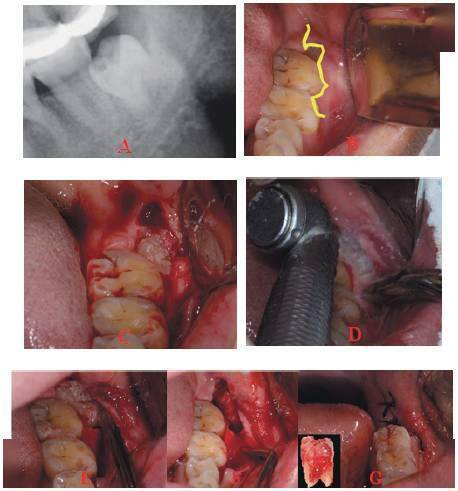

[病例分享]两例垂直高位阻生的智齿拔除

【智齿拔除病例】 一例垂直高位阻生的智齿拔除